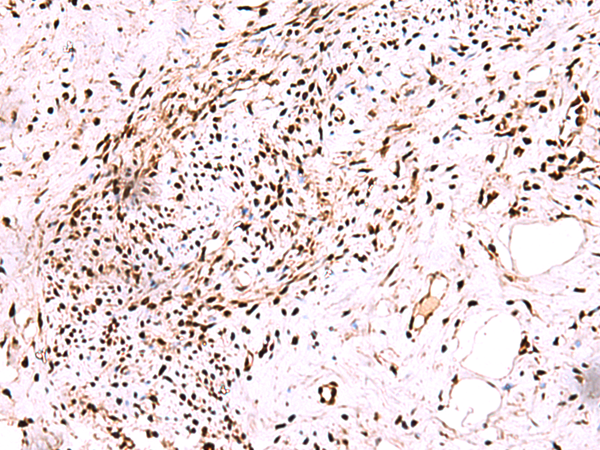

IHC positive control: |

Human cervical cancer and Human ovarian cancer |

IHC Recommend dilution: |

50-300 |